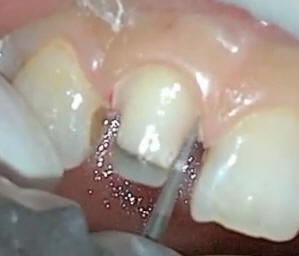

Los hombros en esmalte

son muy marcados |

Con una punta de oxido

de aluminio se redondea el hombro y se pule para una mejor

adaptación de la porcelana |

Levando el hombro

a subgingival solo en vestibular |

Con puntas de diamante

de grano extrafino se elimina el esmalte sin soporte en mesial y distal |